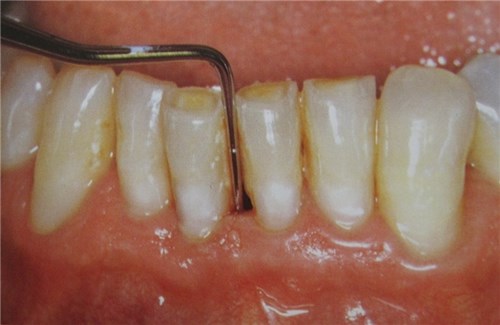

Đó là căn bệnh cực kỳ mất thẩm mỹ và là nguyên nhân gây hôi miệng. Có nhiều nguyên nhân gây ra bệnh. Bạn nên biết để đề phòng căn bệnh này. Bệnh đó là: Tụt lợi.

Tụt lợi là quá trình lộ bề mặt chân răng do sự di chuyển về phía chóp chân răng của lợi. Hiện tượng này còn khiến khoảng cách các kẽ răng ngày càng lớn, tạo điều kiện cho vi khuẩn tích tụ gây mất thẩm mỹ và hôi miệng. Răng trở nên nhạy cảm và dễ bị tổn thương hơn. Bên cạnh đó, các mô nâng đỡ và phần cấu trúc xương cũng có nguy cơ bị hư hại dẫn đến rụng răng.

Bệnh gây mất thẩm mỹ răng và hôi miệng. (Ảnh: Internet)